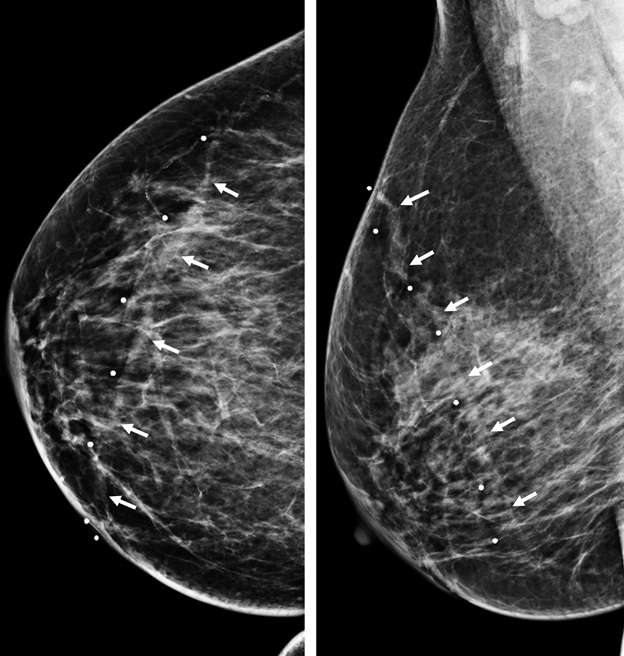

Figure 3A. Superficial thrombophlebitis. Mammographic CC (left) and MLO (right) views of the right breast in a 65-year-old woman with a cord-like palpable abnormality show a dilated, noncalcified vessel spanning all quadrants breast as highlighted by the skin BB markers (and arrows).